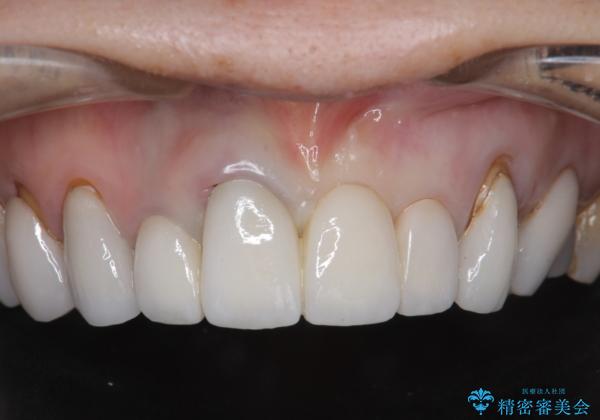

[ セラミック治療 ] 歯ぐきの際の黒ずみを改善したい

- 歯ぐきとセラミックの間の黒ずみが目立つので、きれいに治してほしい。と希望され来院されました。

歯ぐきの位置が変化しクラウン下の歯が見えるようになってしまったことで、審美障害が生じている状態です。

クラウンマージンの再設定を行うことで、黒ずんだ部分を再度覆い、審美障害を改善します。

- 52.8万円(ジルコニアクラウン×4・仮歯×4)費用は治療当時の料金となります

歯ぐきの位置の経年的な変化は、誰にでも起きうる変化です。

強いブラッシングや電動歯ブラシの当て過ぎなども原因の一因となることがあります。